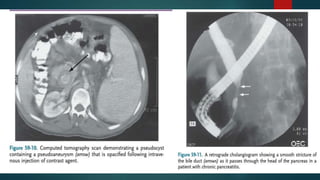

3. CT –

 Grading can be done on CT / USG into Normal, Equivocal , Mild-moderate & Severe

 Findings in chronic pancreatitis – Duct dilatation

Duct obstruction

Parenchymal heterogenity

Irregular contour

Calcification

5. ERCP –

 Diagnosis based on abnormalities in main pancreatic duct & side branches

 CHAIN OF LAKES Appearance

TESTS FOR PANCREATICSTRUCTURE – 1. Plain abdominal radiography –  Diffuse pancreatic calcification is specific  MC in alcoholic , late onset idiopathic , hereditary , tropical pancreatitis 2. Abdominal USG –  Difficult to distinguish age related variability form chronic pancreatitis 3. CT –  Grading can be done on CT / USG into Normal, Equivocal , Mild-moderate & Severe

 Findings inchronic pancreatitis – Duct dilatation Duct obstruction Parenchymal heterogenity Irregular contour Calcification 4. MRI –  Duct Visualisation improved by secertin administration 5. ERCP –  Diagnostic as well as therapeutic  Risk - 5%  Diagnosis based on abnormalities in main pancreatic duct & side branches